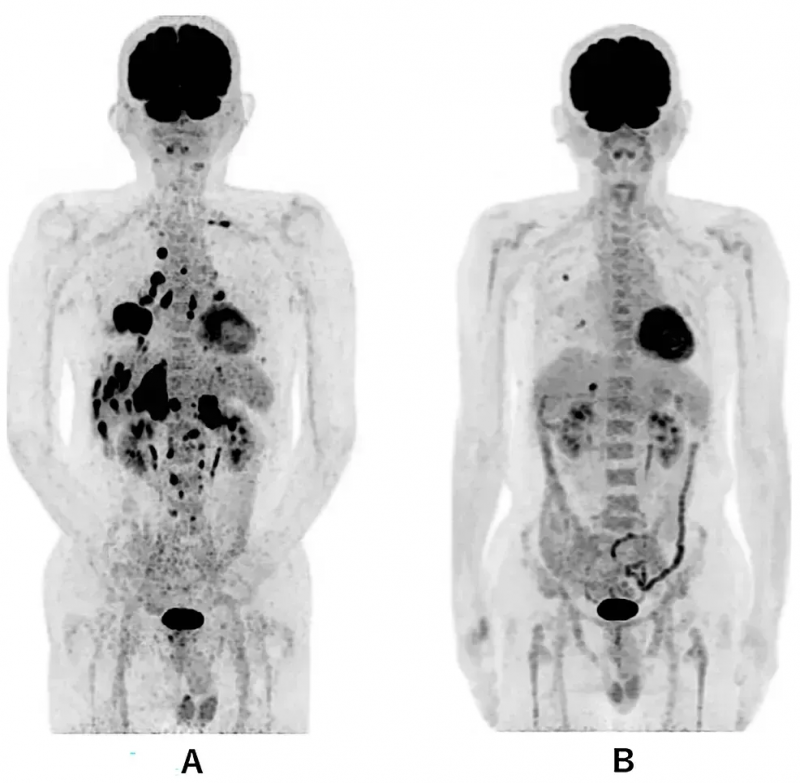

影像学检查显示:治疗前胸部CT可见原发性右下肺癌伴左右胸腔积液,治疗第114天肺部肿瘤明显缩小。更为惊喜的是,治疗前PET-CT提示除右下肺原发灶外,存在全身广泛转移(包括双侧肺内多发转移、多发肝转移、双侧肾上腺转移及多发骨转移),而治疗第479天仅残留右肺1.0cm、肝脏1.7cm两处转移灶,其余病灶均恢复正常(详见下图)。

▼WT1-DC疫苗治疗前后全身PET-CT对比

▲图源“Cureus”,版权归原作者所有,如无意中侵犯了知识产权,请联系我们删除